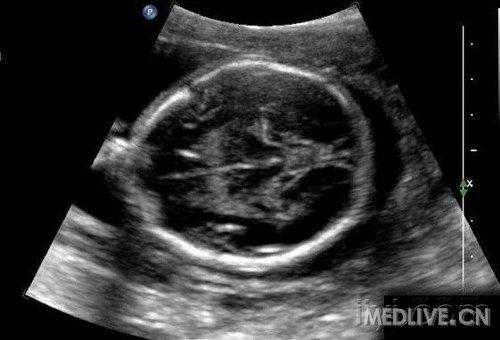

7、孕11-12周:可以分辨宝宝脊柱,头面耳廓开始显现,外生殖器开始发育,但是不能辨别男女。可以诊断一些明显畸形(例如无脑儿)

8.孕13-27周均属于中期妊娠。在此期间可以检测胎儿的生长发育情况,了解胎儿构造及羊水胎盘情况。

a.头面部